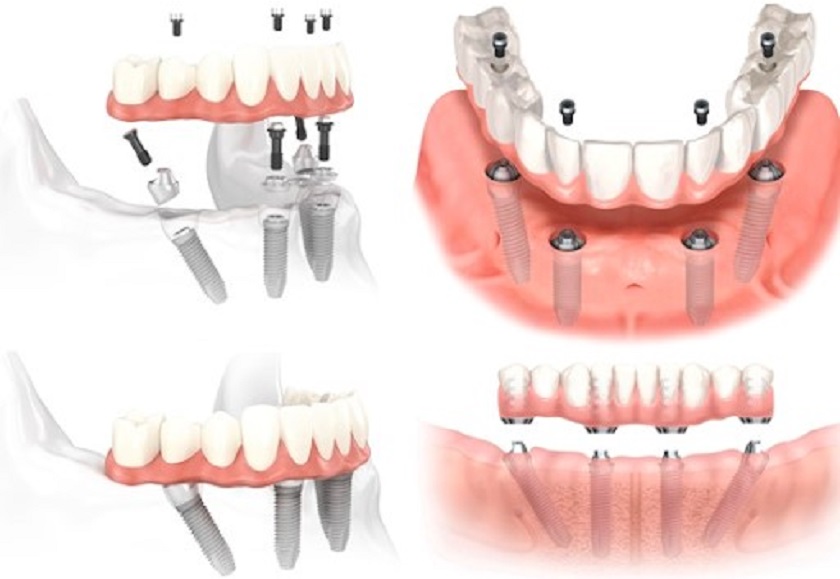

Trong kỹ thuật này, bác sĩ sẽ cấy ghép 4 trụ Implant vào trong xương hàm của khách hàng (quá trình cấy ghép được chia làm 2 lần, mỗi lần cắm 2 trụ Implant để đảm bảo an toàn cho khách hàng). Tiếp đó là thực hiện gắn hàm giả lên trên để khôi phục thân răng sau một thời gian khi mà quá trình tích hợp xương đã hoàn thiện và trụ đã bám chắc chắn trong xương hàm.

Hình ảnh mô phỏng kỹ thuật trồng răng Implant all on 4